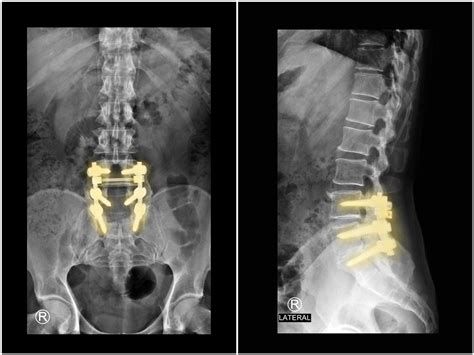

시술 및 수술적 치료

- 6주 이상의 보존적 치료에도 증상이 호전되지 않거나, 하지 마비, 근력 약화, 보행 장애, 대소변 장애 등 신경학적 악화가 동반될 때 수술이 권장됩니다.

- 수술적 치료(예: 디스크 절제술, 협착 부위 감압술, 유합술 등)는 신경 압박을 직접적으로 해소하여 빠른 증상 개선이 가능합니다.

- 최소침습 수술은 회복이 빠르고, 증상 개선 효과가 크지만, 환자 상태에 따라 수술 범위와 방법이 달라질 수 있습니다.

- 수술 후에도 생활습관 개선과 재활이 중요하며, 일부 환자에서는 증상이 완전히 사라지지 않거나 재발할 수 있습니다.